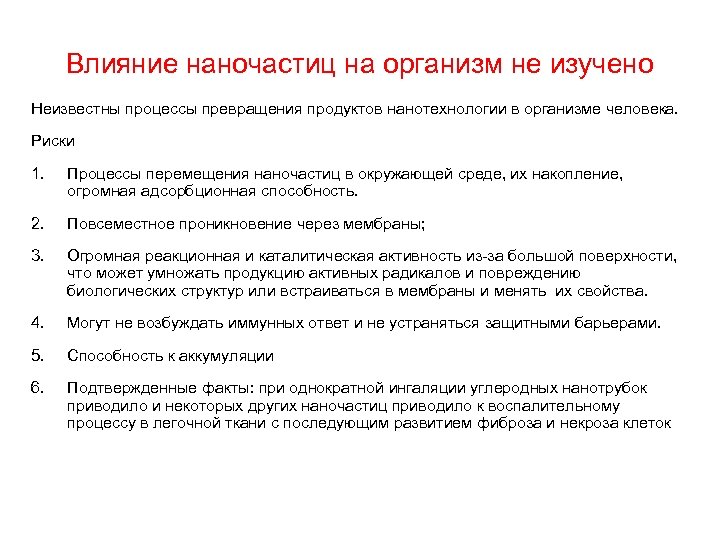

Особенности профессиональной патологии на современном этапе: 1. Ликвидация многих предприятий. 2. Развитие новых отраслей, технологий, использование новых химических соединений, влияние на организм которых не изучено, широкое воздействие электромагнитных волн. 3. Развитие частного производства: 81% частная собственность 12% государственная собственность. 7% другие виды собственности 3. Отсутствие тяжелых форм профессиональной патологии в связи с уровнем концентраций вредных веществ и вредных факторов на уровне ПДК или ПДУ. Изменение течение профзаболеваний. Возможно многие заболевания имеют профессиональную этиологию. 4. Наличие общей патологии, которая может быть обусловлена производственными вредностями. 5. В настоящее время стирается грань между производством и окружающей средой: бытовая химия шум магнитные поля видеодисплейные терминалы (компьютеры) нанотехнологии

Особенности профессиональной патологии на современном этапе: 1. Ликвидация многих предприятий. 2. Развитие новых отраслей, технологий, использование новых химических соединений, влияние на организм которых не изучено, широкое воздействие электромагнитных волн. 3. Развитие частного производства: 81% частная собственность 12% государственная собственность. 7% другие виды собственности 3. Отсутствие тяжелых форм профессиональной патологии в связи с уровнем концентраций вредных веществ и вредных факторов на уровне ПДК или ПДУ. Изменение течение профзаболеваний. Возможно многие заболевания имеют профессиональную этиологию. 4. Наличие общей патологии, которая может быть обусловлена производственными вредностями. 5. В настоящее время стирается грань между производством и окружающей средой: бытовая химия шум магнитные поля видеодисплейные терминалы (компьютеры) нанотехнологии